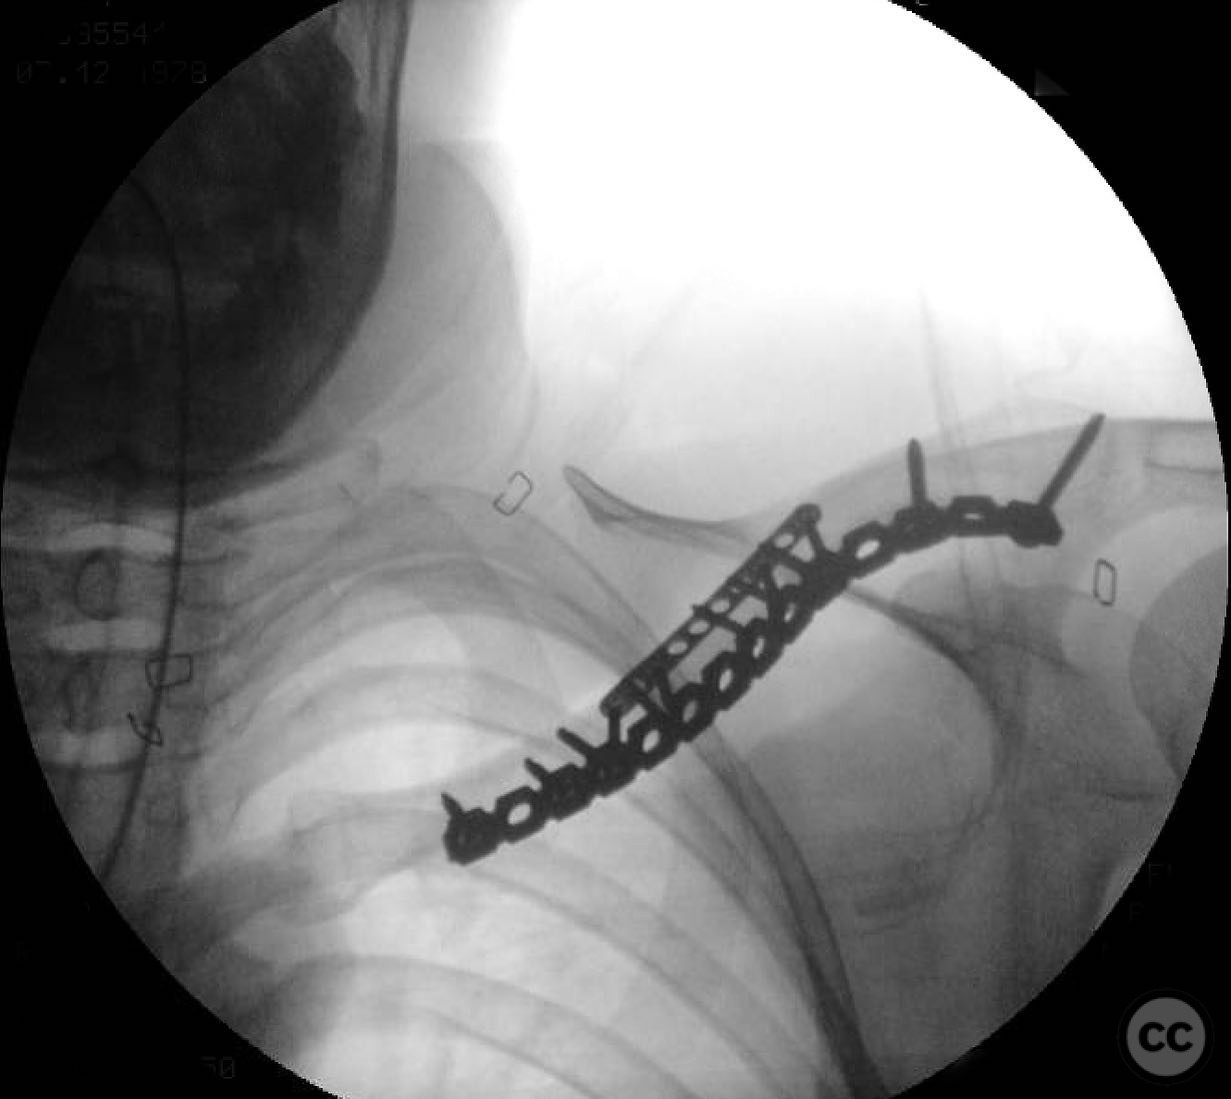

During the procedure, anatomic reduction of the butterfly fragments was achieved using 2.4mm lag screws for interfragmentary compression. The main segment reduction proved challenging due to instability; hence, a 2.4mm "clamp replacement plate" was temporarily used to maintain reduction. A reconstruction plate was contoured and applied to the anterior inferior clavicle, providing a neutralization construct. Absolute stability was achieved, anticipating primary bone healing.

Orthopaedic implants used:   2.4mm lag screws, 2.4mm clamp replacement plate, reconstruction plate.